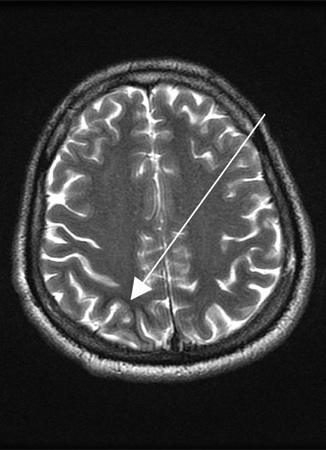

Entamoeba histolytica brain abscess

Reproduced from Transactions of the Royal Society of Tropical Medicine and Hygiene (2007); used with permission